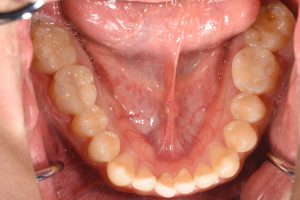

治療後

この患者様の場合

1回目にカウンセリング

2回目に型取り

3回目にセラミックのセット

の合計3回で治療終了となりました。